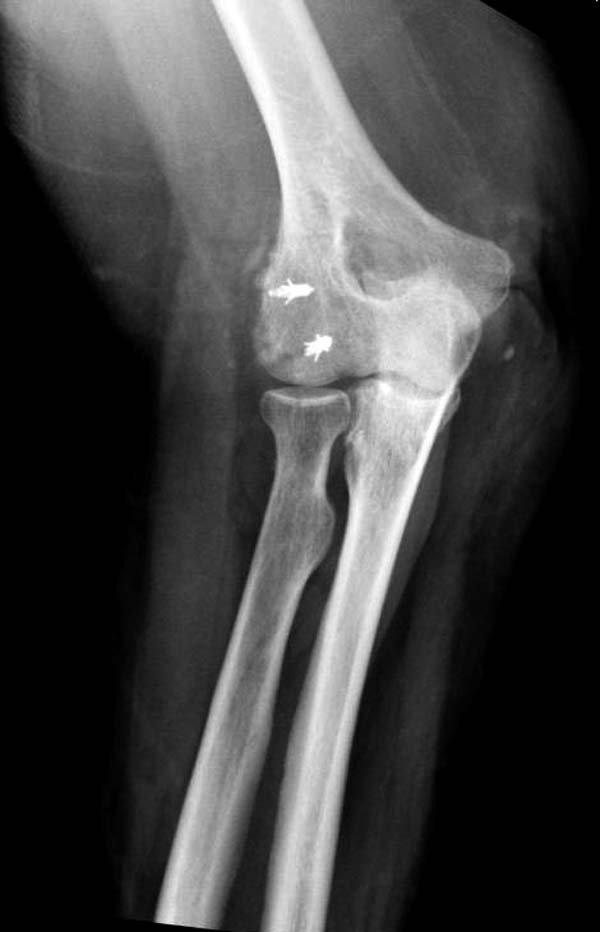

Снимки: 1-2 вывих, 4-5 вторичное смещение в гипсе, реконструкция

латеральной связки и капсулы 13-14, повторный вывих после реконструкции,

Вложение не в текстовом формате было извлечено…

Имя     : 4 Elbow dislocation post reduction.jpg

Тип     : image/jpeg

Размер  : 51750 байтов

Описание: отсутствует

Url     : http://weborto.net:8080/pipermail/ortho/attachments/20131212/4b05a6a3/attachment-0008.jpg